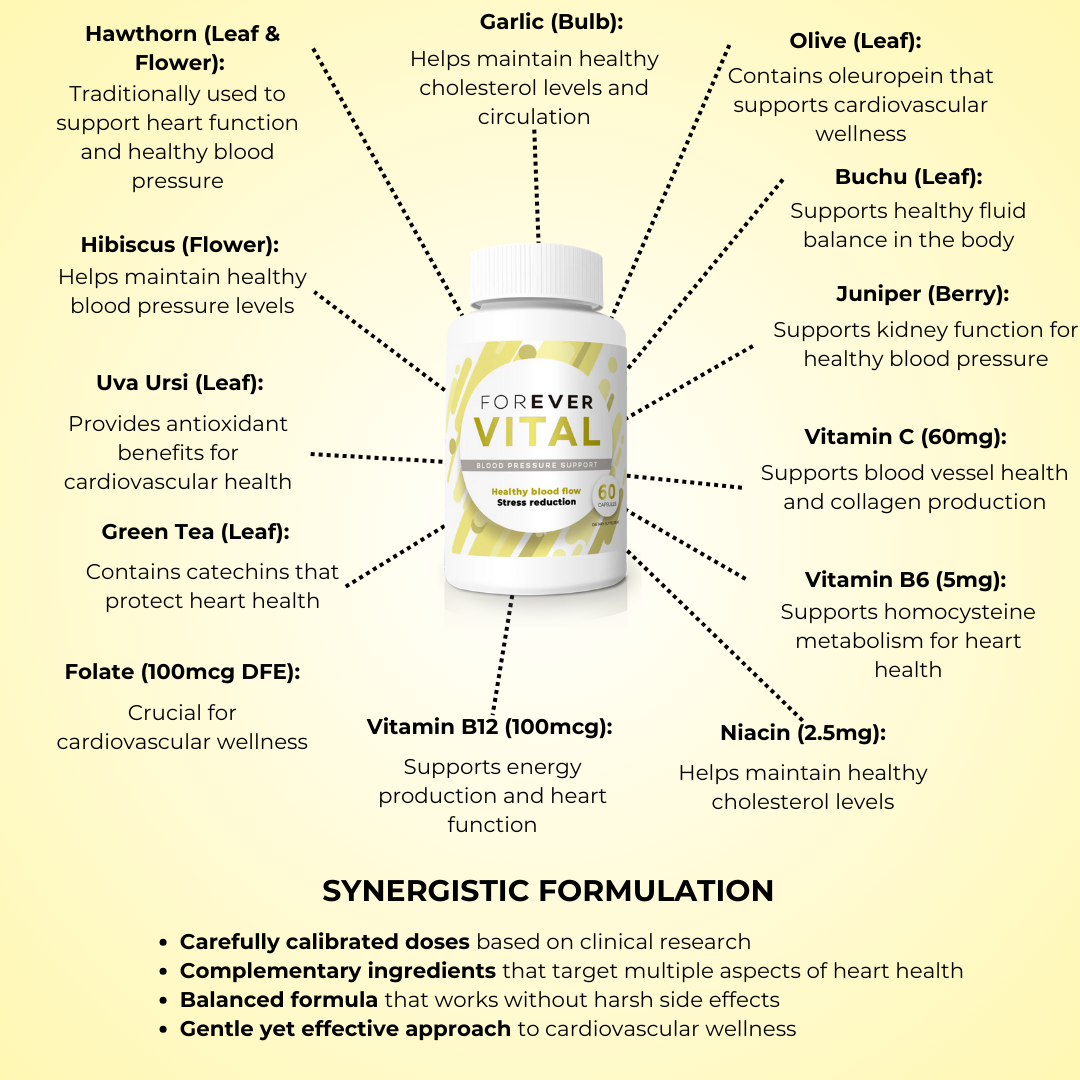

PREMIUM CARDIOVASCULAR COMPLEX

Our proprietary 620mg blend combines science-backed ingredients for comprehensive heart support: